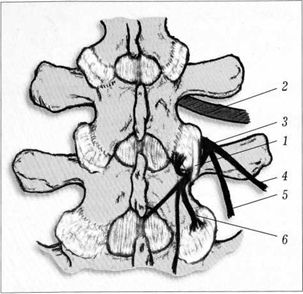

Межпозвонковый, фасеточный, или дугоотростчатый, сустав (art. zygapophyseales) образуется верхним и нижним суставными отростками и окружен суставной капсулой, которая прикрепляется по краю суставного хряща. Дугоотростчатый сустав иннервируется медиальными веточками задней (дорсальной) ветви спинномозгового нерва. Каждая медиальная веточка направляется вокруг основания верхнего суставного отростка и проходит через углубление, образованное lig. mamilloaccessorius. В этом месте отходят маленькие веточки нерва к капсуле фасеточного сустава. Медиальная нисходящая веточка идет каудальнее и, разделяясь на несколько частей, иннервирует мышцы, связки и частично нижележащий межпозвонковый сустав [2, 3, 5, 21] (рис. 1). Таким образом, иннервация каждого дугоотростчатого сустава осуществляется по меньшей мере с двух уровней (по некоторым данным — с трех). Например, дугоотростчатый сустав L4-5 иннервируется из корешковых нервов уровней L3 и L4 (возможно, L2).

Рис. 1. Схема иннервации дугоотростчатых суставов.1 — lig. mamilloaccessorius; 2 — спинномозговой нерв; 3~6 — ветви спинномозгового нерва: 3 — дорсальная ветвь, 4 — латеральная, 5 — промежуточная, 6 — медиальная веточки.